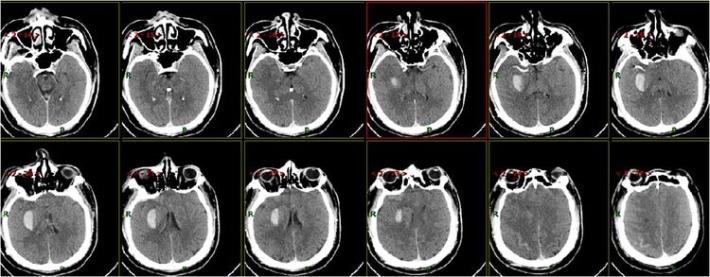

术后即刻复查头部CT

患者术后1天,左侧肢体肌力0级,NIHSS评分:12分,复查头部CT:右侧基底节区出血,范围约22mmX49mm,请脑外科会诊:做好立体定向穿刺准备,注意观察患者病情变化,密集复查头部CT。

术后3天复查头部CT

术后7天复查头部CT

术后15天复查头部CT

术后21天复查头部CT